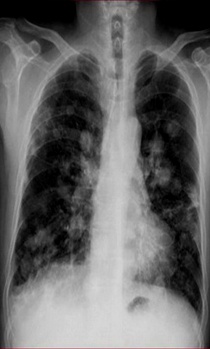

满肺可见“满天星”,根据公式诊断肺转移瘤